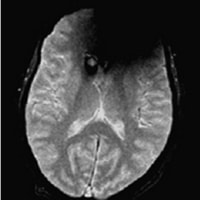

患者様を案内又は搬送する際は、患者様の金属の有無について十分注意をお願いします。金属が体内に入っている方や、 身につけている方は写真上に影響が出ると同時に体内金属が動いたり、発熱したりする場合があり危険な場合があります。 金属があった場合の症例を提示します。

磁気健康器具による影響